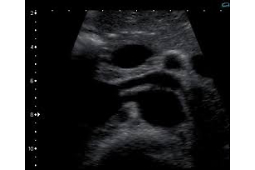

- Wartość rynkowa usług medycznych w 2015 roku sięgała 39,5 mld złotych. Wśród usług medycznych, za które płacimy sami, wysoko na liście są badania diagnostyczne. Największa liczba osób postanowiła wykonać prywatnie badanie USG tętnic / żył kończyn dolnych (7,31%), kolejnym popularnym badaniem było USG Dopplera tętnic szyjnych / kręgowych, a za nim znalazła się ultrasonografia jamy brzusznej (0,84%) – pisze „Głos Koszaliński”.